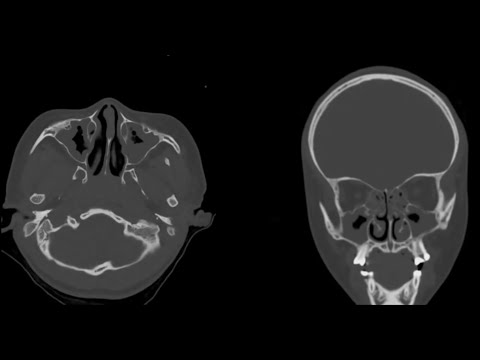

Sinüzit Teşhisi ve Tedavisi